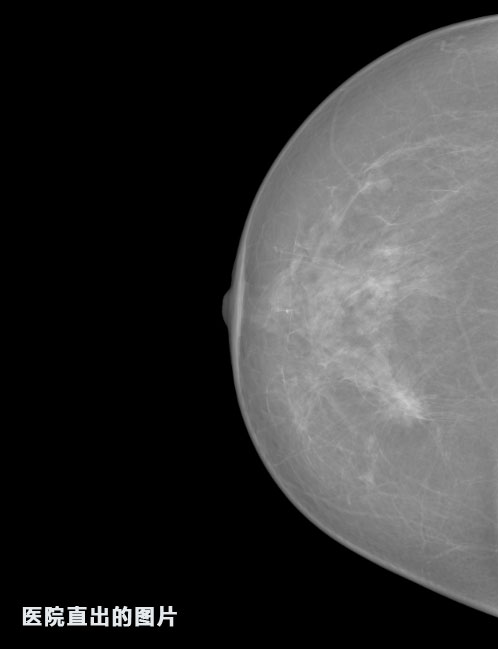

識(shí)別報(bào)告:

1.發(fā)現(xiàn)良性鈣化,可能性為19.88%---位置框指數(shù):[1796.0867 1359.8237 2058.1372 1582.5334]

2.發(fā)現(xiàn)惡意鈣化的可能性為15.18%---位置框指數(shù):[1789.4733 1365.9951 2063.7698 1576.0613]

3.發(fā)現(xiàn)惡意鈣化的可能性為12.45%---位于框指數(shù):[1859.3987 1422.3184 2006.5494 1528.2698]